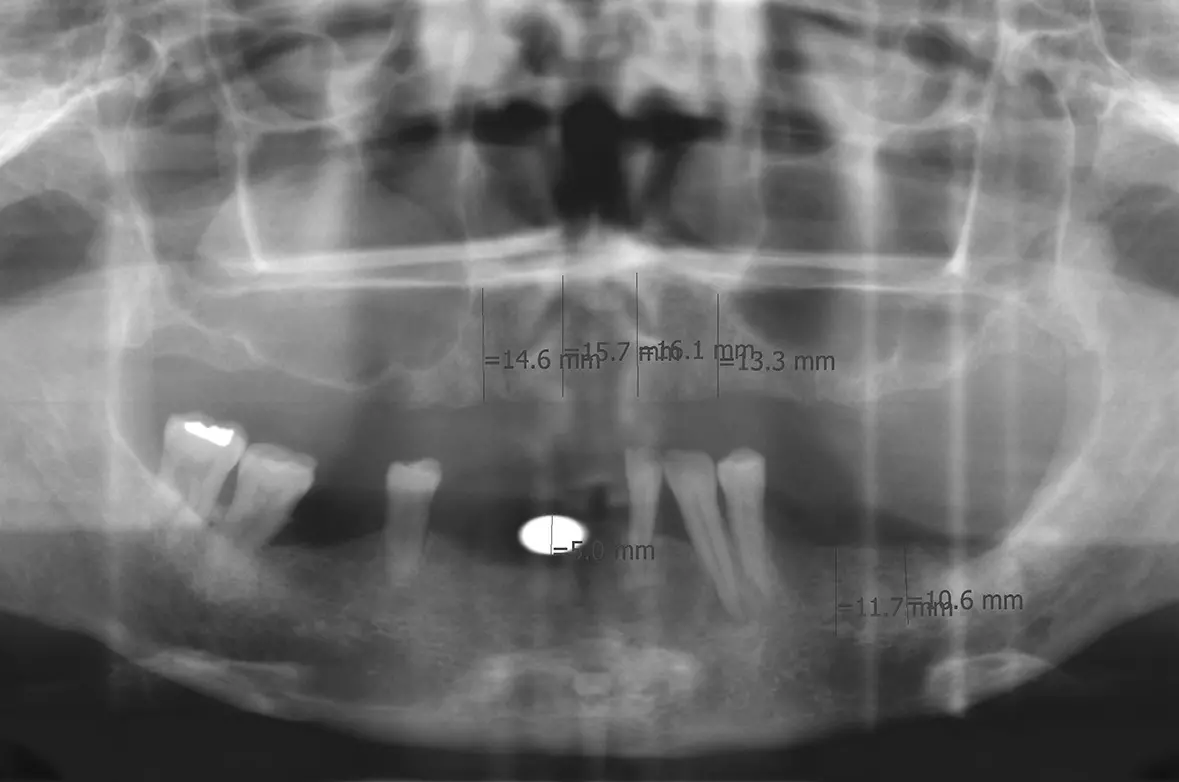

Abb. 1: OPG vor Behandlungsbeginn. Dr. Michael Leistner

Abb. 1: OPG vor Behandlungsbeginn.

Die Knochensituation im Oberkiefer war ausreichend für 4 Implantate zwischen 13 und 23 (2 x Zeramex XT 4,2/10 mm und 2 x 4,2/12 mm). Die Freiendsituation im Unterkiefer wurde mit 2 Implantaten im 3. Quadranten gelöst (2 x Zeramex XT 4,2/10 mm). Für den restlichen Unterkiefer war eine festsitzende Brücke von 34, 33, 32, 44, 46 auf 47 geplant. Da neu und seit diesem Zeitpunkt verfügbar, kamen verschraubte Docklocs® Zirkon Abutments aus Zirkonkeramik zum Einsatz.